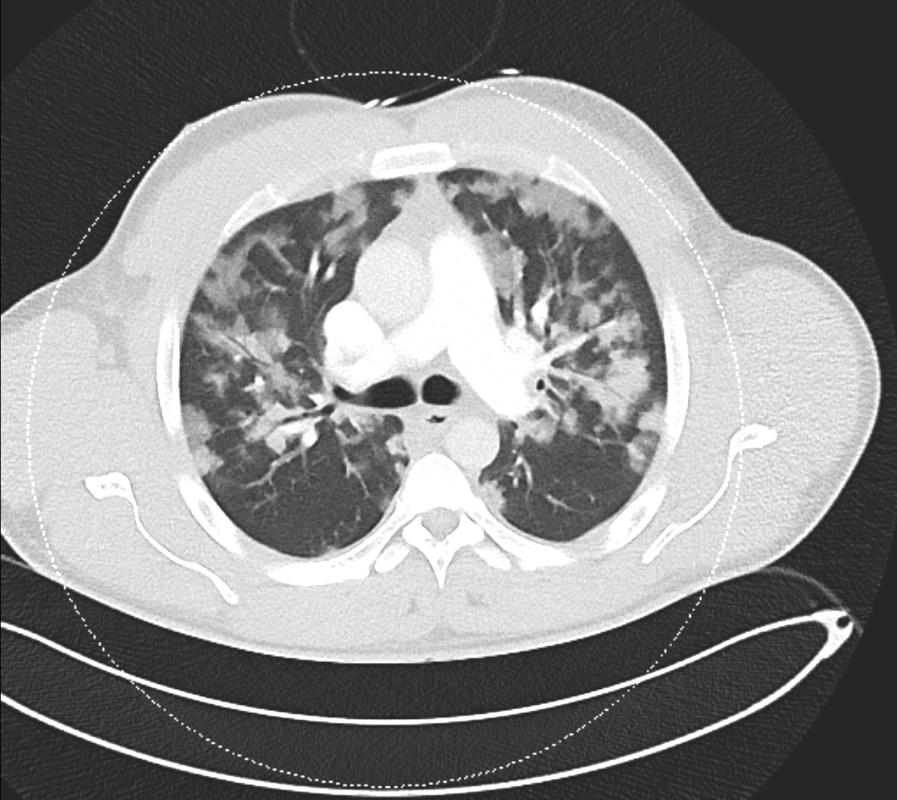

CT扫描排除了肺栓塞,但显示出心脏增大,右心室扩张,表明存在肺阻力。肺部所有叶段均表现出弥漫性浸润性病变,与肺水肿和潜在感染一致。磨玻璃样影进展到实变提示肺泡损伤和微出血,增加了急性呼吸窘迫综合征(ARDS)的可能性。